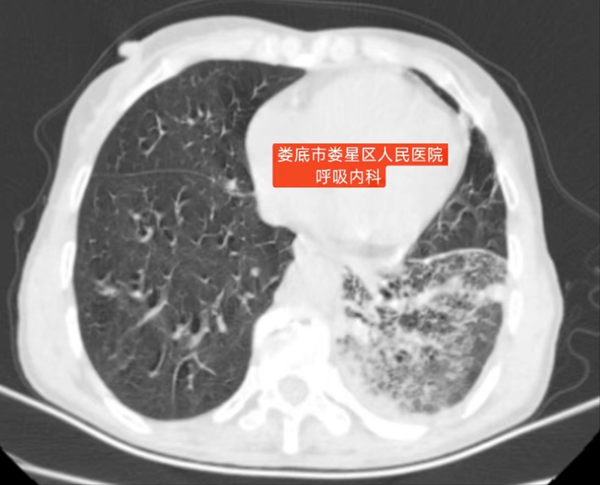

卓越医疗||呼吸与危重症医学科:支气管镜锁定罕见诺卡菌挽救七旬老人